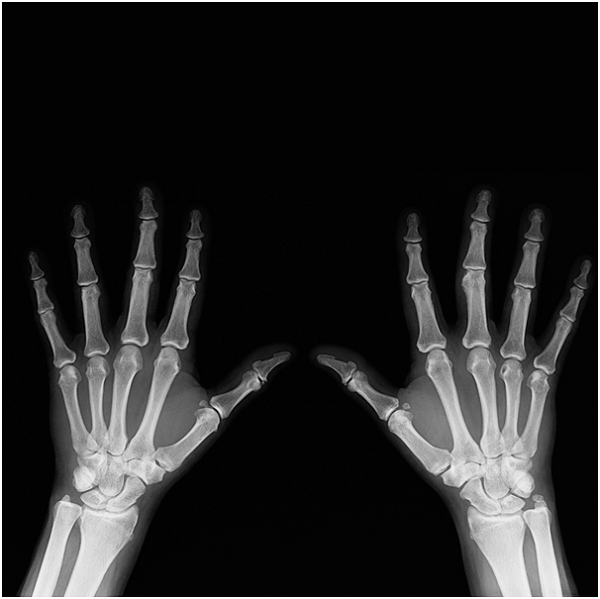

Hand surgery in Singapore is not easy, considering the risks of undergoing one. And if you need this treatment, ask this question to know what you should do. When I asked them this question, they told me about getting enough rest and eating healthy food. I followed them, giving me enough time to prepare.